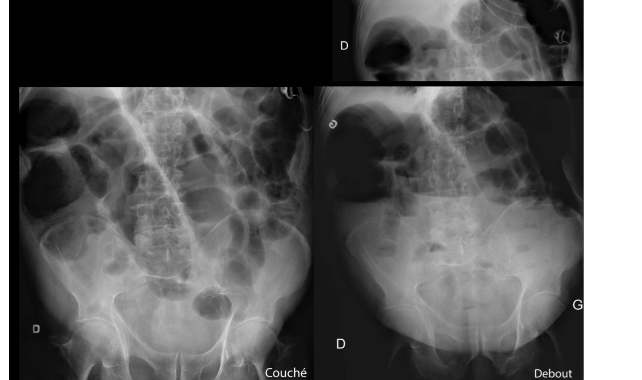

Q

A

obst grêle,

ya meme des clips d’appendicectomie qui fitte avec obst par ADHÉRENCES